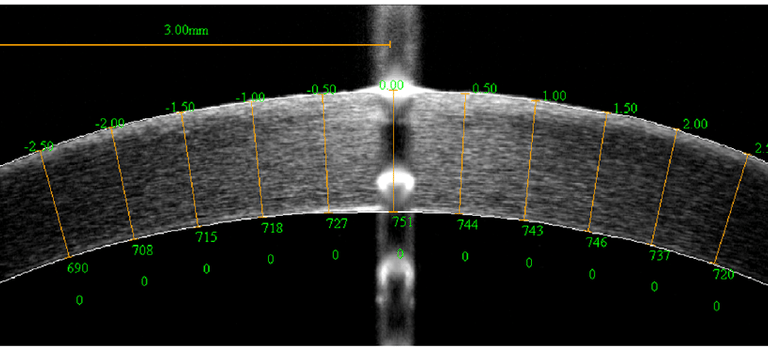

A paquimetria é um exame que mede a espessura da córnea, uma informação crucial para o diagnóstico de condições como o ceratocone e para a avaliação pré-operatória em cirurgias refrativas. O exame é rápido e indolor, realizado com um aparelho que emite uma onda ultrassônica ou luz para medir a espessura corneana com precisão. Esses dados são fundamentais para garantir a segurança e o sucesso de intervenções cirúrgicas nos olhos.